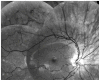

Results: Unresponsive mydriatic pupils with scalloping wisps of persistent pupillary membrane from the iris collarette were an early indicator of this rare genetic disorder in all three cases. Tortuousity of retinal arterioles was the main posterior pole finding, apparent during the first year of life and with a tendency to increase with age. In one case, it progressed to an aneurysmal-like state with breakdown of the blood-retinal barrier.